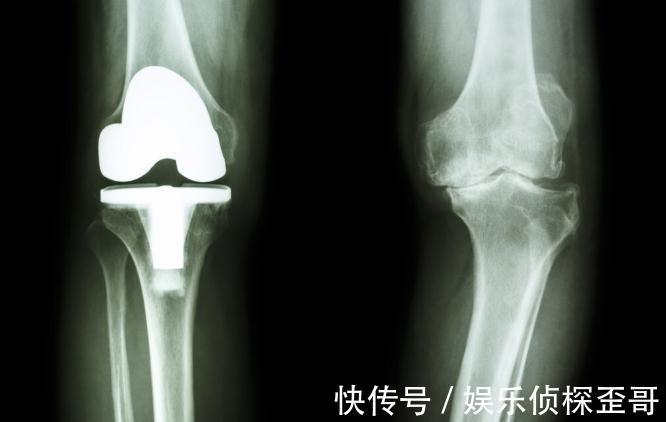

不同的关节炎致残的风险有高有低,都不容忽视,晚期的关节炎患者,如果结构发生了严重破坏,关节活动能力严重丧失,这就意味着残疾的临近。这时候,要远离残疾就只有“破而后立”,去除原来的关节结构,置换人工关节!

人工关节置换术,能帮助晚期关节炎患者去除疼痛和恢复关节功能。但有些患者纳闷,有这种“一劳永逸”治疗关节病的方法,医生为何要藏私,非要等患者饱受疼痛折磨后才建议使用?今天我们就来看看原因,了解人工关节置换术的真面目!

⑤对于终末期严重的关节炎患者,保守的治疗已经无法让关节功能恢复时,就要考虑接受重建性的手术,人工关节置换术就是代表。

其实很简单,就是能让终末期关节病患者的关节“起死回生”。关节病的终末期,患者关节内的结构遭到了严重破坏,即便控制住症状,结构损伤产生的关节功能障碍也无法恢复,而且靠药物和微创修复手术,也无法让关节恢复正常。

简单说,就是关节报废了,只有把报废的关节换成新的关节,关节才能恢复活动能力!